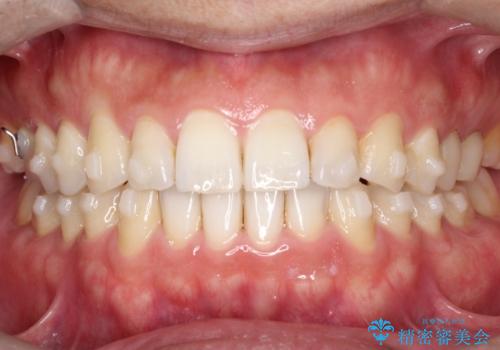

- 前歯の隙間を主訴に来院されました。

マウスピース矯正にて、隙間を綺麗に閉じることができ満足していただきました。

前歯の隙間を閉じる際は、前歯部の突き上げが懸念されるため、適切な治療計画が必要となります。